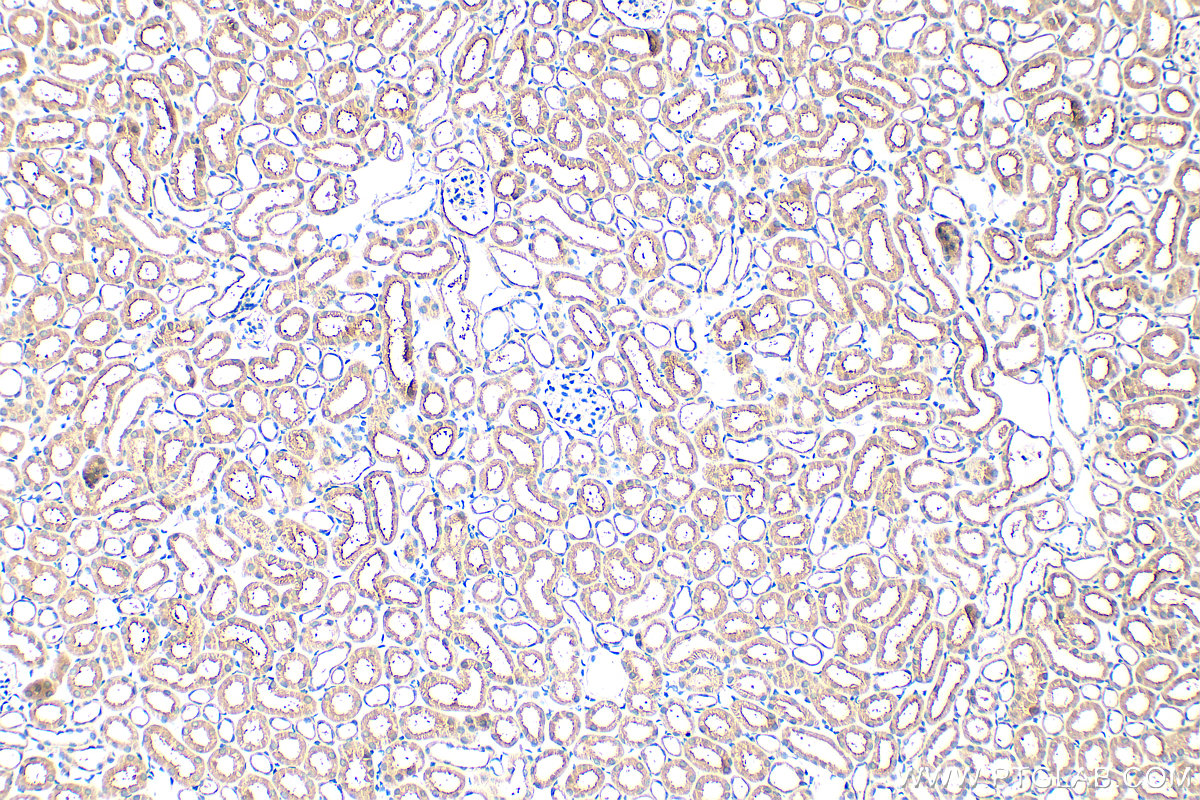

| Positive IHC detected in | mouse kidney tissue, mouse small intestine tissue Note: suggested antigen retrieval with TE buffer pH 9.0; (*) Alternatively, antigen retrieval may be performed with citrate buffer pH 6.0 |

| Immunohistochemistry (IHC) | IHC : 1:50-1:500 |